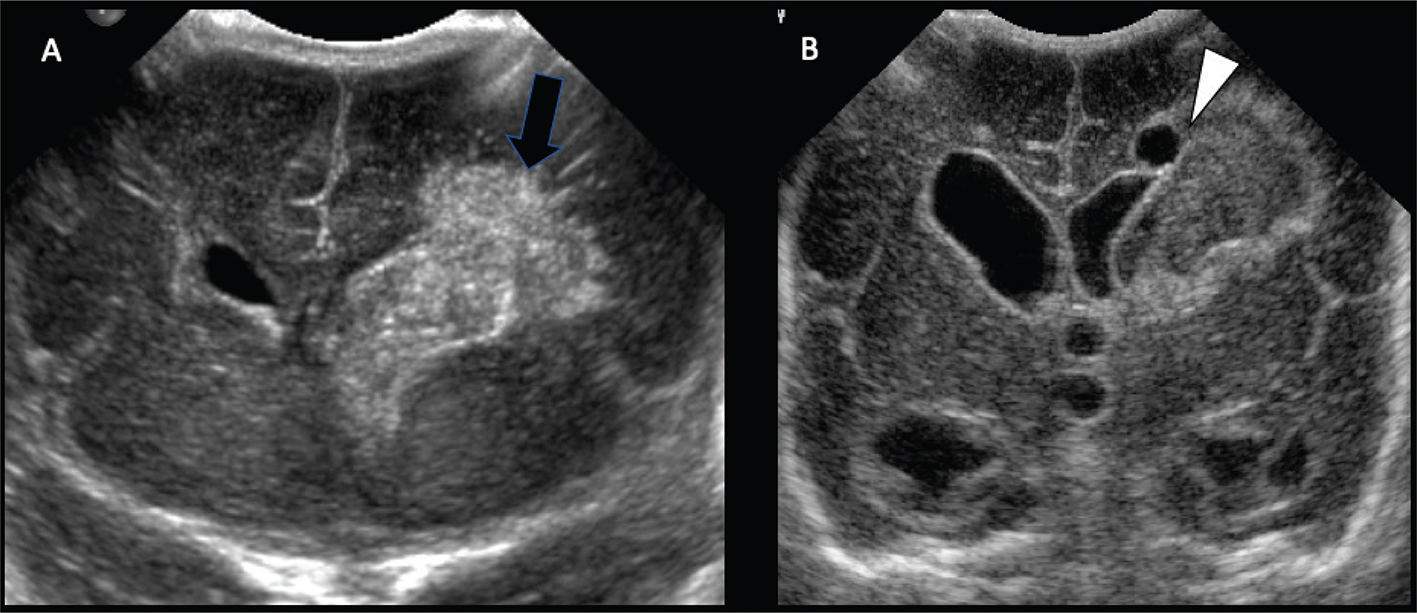

Acute phases of fetal stroke, such as in case of congenital heart disease or twin-twin transfusion syndrome (TTTS), may only rarely be detected prenatally. Fetal stroke often manifests with the chronic features of unilateral ventriculomegaly and volume loss with or without associated hemorrhage (Figures 1 and 2).

Fig 1

Figure 1. Acute and chronic fetal infarctions. 29 weeks of gestation fetus with a chronic stroke in the right hemisphere. (A) Axial HASTE (Half Fourier Singleshot Turbo Spin-Echo) and (B) Gradient Recall Echo (GRE) images showing unilateral enlargement of the right lateral ventricle, with periventricular white matter loss (white arrow) and linear blood staining (black arrowhead). 21 weeks of gestation fetus with congenital heart disease with acute stroke in the right hemisphere. (C) Axial DWI and (D) ADC map showing areas of reduced diffusion in the left ACA and MCA territories (black arrow) with questionable infarct in the right MCA territory (white arrowhead). Case courtesy of Dr. Tamara Feygin, Department of Radiology, Children’s Hospital of Philadelphia.